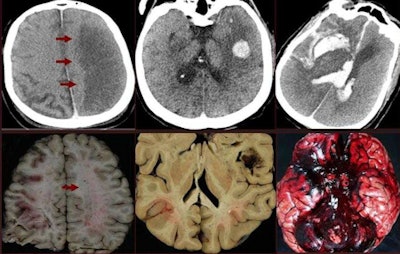

Interpretation of postmortem images requires training to differentiate normal postmortem changes from premortem pathologies. Potential CT findings can be obscured by normal postmortem body changes such as brain swelling, gas formation, and lung edema, so it's important to scan as close to the time of death as possible.

Normal postmortem findings that should be considered when reporting CT findings include the following: loss of differentiation between gray and white matter, brain edema and swelling, putrefaction (gas formation), sedimentation of blood cells, clot formation in the heart and great vessels, and collapsed lungs.